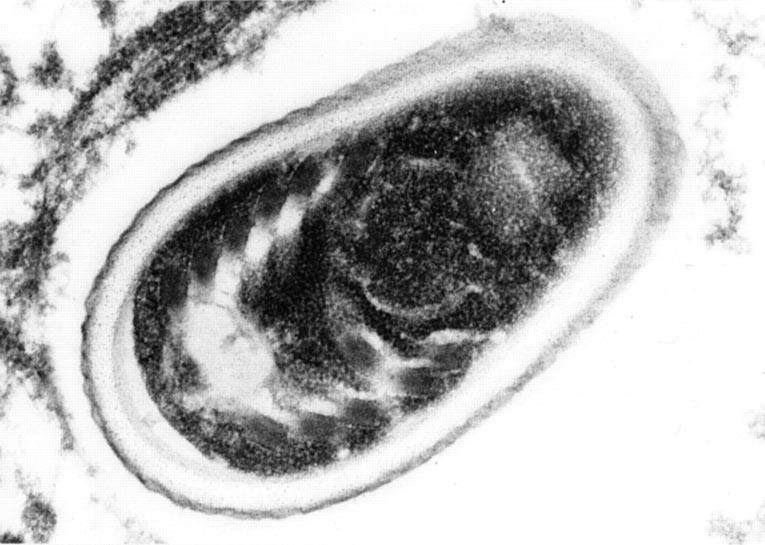

FIGURE 7

Transmission electron micrograph of a section from a necrotic area of adrenal gland showing an Encephalitozoon cuniculi spore containing a polar tube arranged in a single row with six coils. (Lead citrate, uranile acetate; original magnification, 30000×)